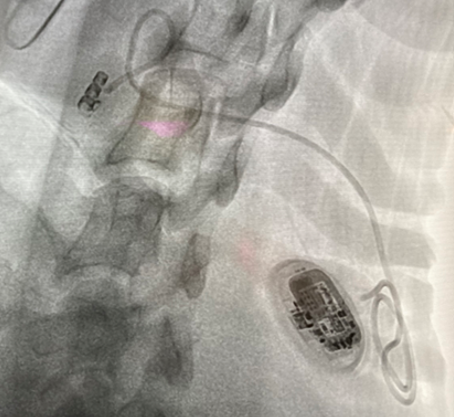

X-ray image of the device implanted in a sheep (IMMR)